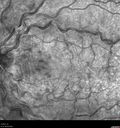

25 year old man with 1 week vision loss 20/16 OD 20/100 OS - CRVO

Heterozyrous for Factor V Leiden - Required 3 years of Lucentis - VA improved to 20/30. Able to stop therapy